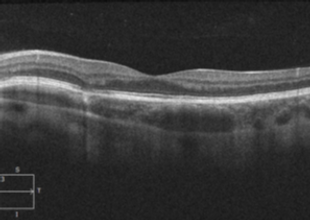

Patient Presentation: A 23-year-old obese female was diagnosed with idiopathic intracranial hypertension (IIH) and referred to neurosurgery for ventriculoperitoneal shunt. A baseline ocular examination was performed prior to the procedure.

On examination, vision was 20/200 in the right eye, and 20/40 in the left eye. There was a right relative afferent pupillary defect. Slit lamp examination was normal.

A dilated fundus examination was performed demonstrating the following: